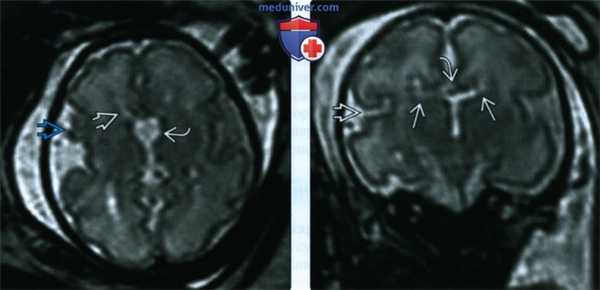

(а) Рисунок коронального среза: отсутствие поперечно располагающегося мозолистого тела и отдаление боковых желудочков друг от друга. Межполушарная борозда простирается до III желудочка. Пучки Пробста содержат парасагиттальные каллозальные волокна, изменившие свое направление.

(б) МРТ, Т2-ВИ, корональный срез: у пациента с дисгенезией мозолистого тела (МТ) определяется признак шлема викинга или головы лося, образованный широко раставленными боковыми желудочками. Выражение гипоинтенсивные волокна белого вещества, расположенные медиальнее боковых желудочков, являются пучками Пробста. Обратите внимание на гетеротопию серого вещества. (а) МРТ, Т2-ВИ, сагиттальный срез: у того же пациента определяется отсутствие мозолистою тела, радиально ориентированные извилины, сходящиеся на высоко посаженном III желудочке. Обратите внимание на непарную переднюю мозговую артерию (ПМА). Передняя комиссура также отсутствует.

(б) МРТ, Т2-ВИ, аксиальный срез: у того же пациента определяются характерное параллельное расположение несходящихся боковых желудочков, что встречается при агенезии мозолистого тела. Выраженно миелинизированные пучки Пробста располагаются медиальнее боковых желудочков.

(а) МРТ, Т1-ВИ, сагиттальный срез: частичная агенезия/ дисгенезия мозолистого тела (АМТ) без признаков ассоциированных аномалий. Задняя часть мозолистого тела отсутствует, но соединение со сводом мозга сохранено. На корональных срезах задних отделов мозга можно было бы увидеть пучки Пробста в то время, как на изображениях срезов передних отделов мозга изменений бы не наблюдалось.

(б) МРТ, Т2-ВИ, корональный срез: АМТ с (шунтированными) межполушарными менингеальными кистами. Обратите внимание на выраженную нодулярную гетеротопию справа по отношению к пациенту. Пучок Пробста сформирован только слева.

3. МРТ при дисгенезии мозолистого тела:

• Т1-ВИ:

о Сагиттальные срезы:

- Частичное или полное отсутствие комиссур, расширение крыши III желудочка

- Аномальная поясная извилина: паттерн лучеобразно расходящихся борозд

- ПК может отсутствовать, быть малых или нормальных размеров

о Корональные срезы:

- Межполушарная борозда спускается вниз до крыши III желудочка

- Пучки Пробста: медиальные парасагиттальные тракты белого вещества, светлее других миелиновых структур на Т1-ВИ, зазубривают боковые желудочки («голова быка» и т.д.)

- Височные рога расщеплены, гиппокамп закруглен

о Аксиальные срезы:

- Параллельные разделенные боковые желудочки, кольпоцефалия

• Т2-ВИ:

о Морфологическая картина идентична Т1-ВИ:

- Пучки Пробста темнее остального белого вещества о Варианты и ассоциированные аномалии развития:

- Высоко посаженный III желудочек

- Частичная агенезия обычно затрагивает задние отделы МТ и ГК

- Множественные межполушарные кисты (менингиальная дисплазия)

- Липомы: нодулярные, криволинейные

- Мальформации кортикального развития (МКР): полими-крогириеподобная кортикальная мальформация (часто параллельно кистам, локализующимся по срединной линии), субкортикальная или перивентрикулярная узелковая гетеротопия